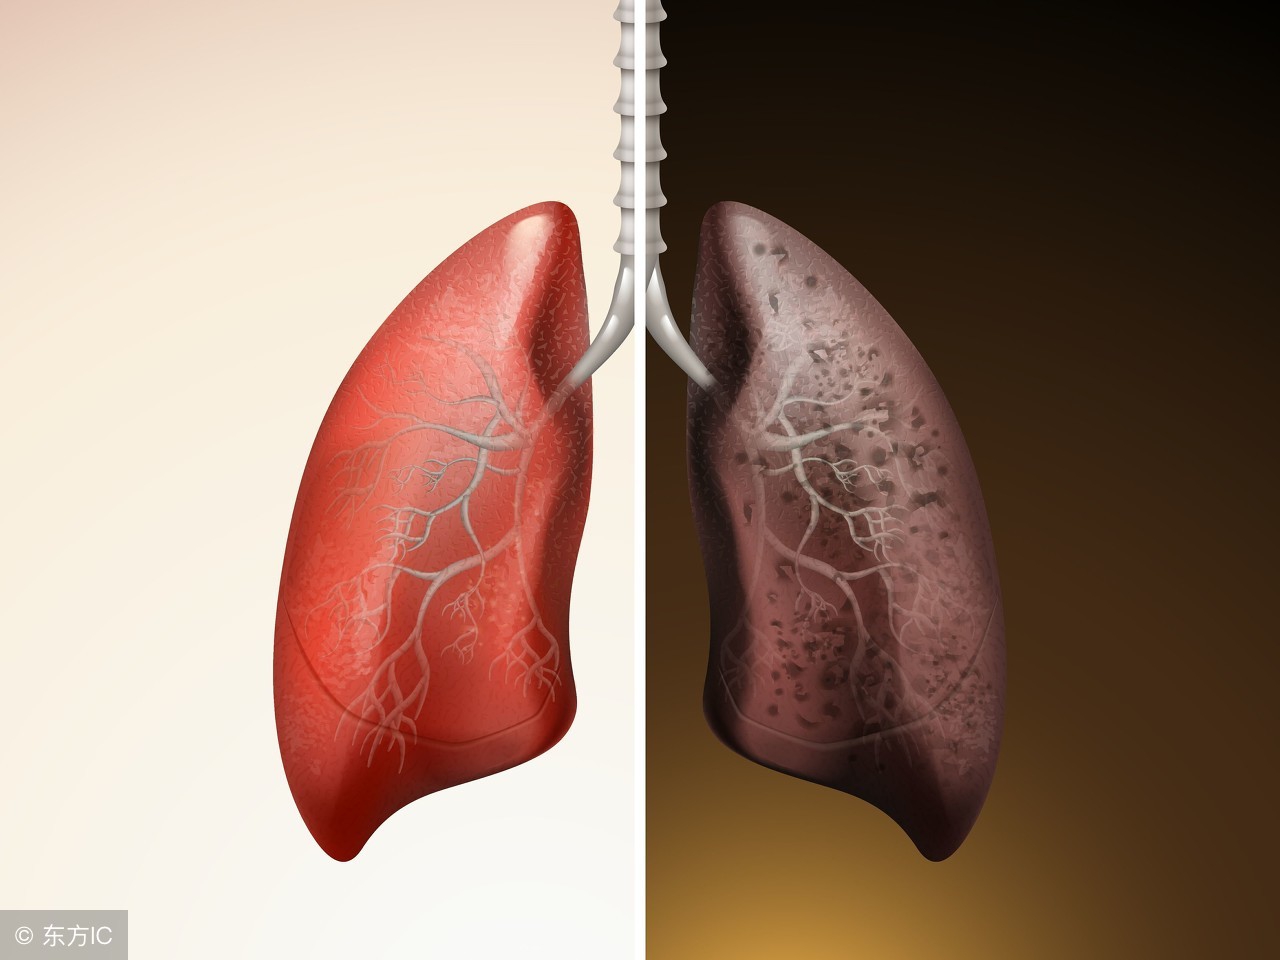

随着社会的发展,人们生活水平的在不断的提升,但是通过调查得出患有肺癌的人数也在不断的增加,肺癌让患者受到了很严重的痛苦,相信大家都想知道,究竟肺癌更倾向于哪类人呢?